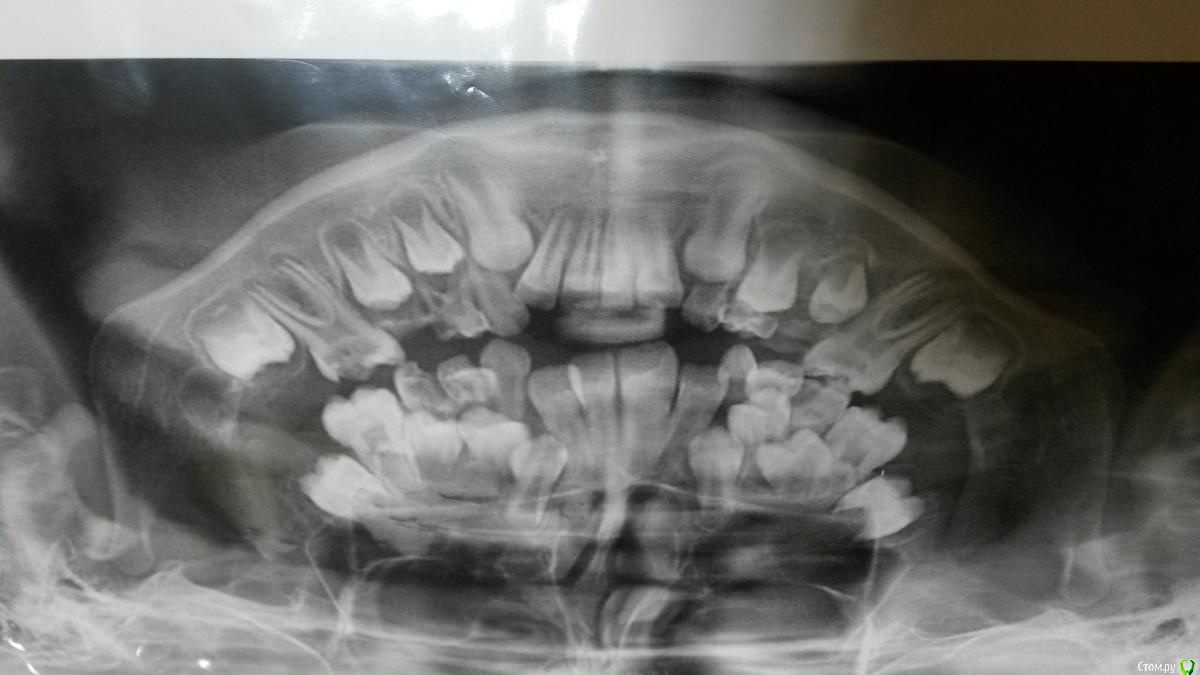

wisto Опубликовано 16 июля, 2015 Поделиться Опубликовано 16 июля, 2015 Очень нужен совет!ребенок 8,5лет -пролечены 73 как кариес(лечили без анестезии).затем74,64 как пульпитные зубы.по словам мамы эти зубы ее не беспокоят,а вот 32болит при надавливании и под вечер.принимают ибуклин дет-все проходит.на приеме все зубы-31,32,73,74,75,36 проверила-на перкуссию,на термопробы реакции нет.верхние тоже.. что это может быть?я думаю-или все-таки 73 беспокоит,или 36 иррадиация,или режется 33 и давит на 32..завтра уже 4день как пьют ибуклин..как можно определить? Ссылка на комментарий

wisto Опубликовано 16 июля, 2015 Поделиться Опубликовано 16 июля, 2015 (изменено) ОПТГ прилагаю Изменено 16 июля, 2015 пользователем wisto Ссылка на комментарий

CRAZYDUCK Опубликовано 16 июля, 2015 Поделиться Опубликовано 16 июля, 2015 А почему ОПТГ до лечения сделана ? я бы 64 вообще уже не лечила -по снимку резорбция корней , а насчет 73 нужно еще прицельный сделать.на 32 проблем не вижу , 6 зубы проблемные . Ссылка на комментарий

CRAZYDUCK Опубликовано 16 июля, 2015 Поделиться Опубликовано 16 июля, 2015 Сделайте прицельный 73 и 74 , может 74 уже просится на удаление . Ссылка на комментарий

wisto Опубликовано 16 июля, 2015 Поделиться Опубликовано 16 июля, 2015 Оптг сделано у ортодонта.64лечить не планируется. Планируется лечение 36 и 46. Ссылка на комментарий